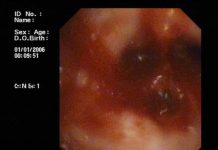

Hình ảnh mô tả phương pháp nội soi cắt u phì đại lành tính tuyến tiền liệt